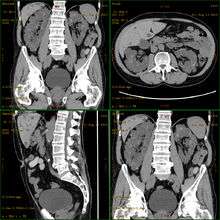

| Polycystic kidneys | |